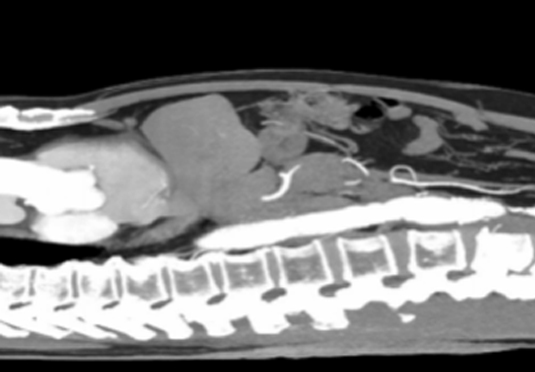

血管新生:激發(fā)周圍組織中的血管生長,過程被稱為血管新生或腫瘤血管化;血管不規(guī)則分布,缺乏正常結(jié)構(gòu)和功能,致血液供應(yīng)不足和缺氧情況。

組織破壞和浸潤:侵襲和破壞正常組織,穿過正常組織的屏障,入侵到其他組織和器官中,形成遠(yuǎn)處的轉(zhuǎn)移,顯示出惡性腫瘤細(xì)胞的擴(kuò)散能力。